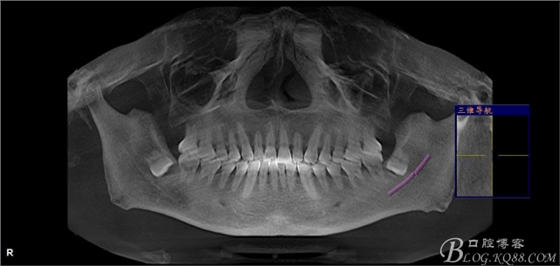

一、術(shù)前CBCT影像資料

圖1. 口內(nèi)38完全埋伏